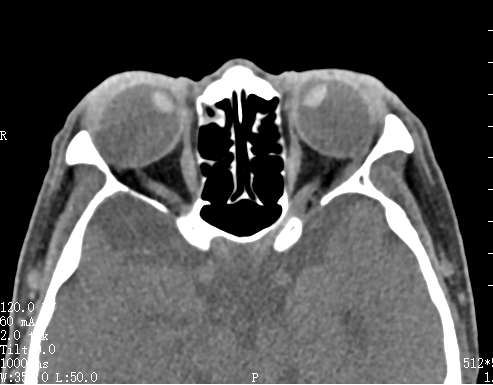

经周炼红教授细致检查,李阿姨被诊断为“高度近视性固定性内斜视”,也称为“重眼综合征”。因其近视度数超过2000,造成眼球异常增长,眼球后极部进行性膨隆突破肌圆锥,导致眼外肌解剖关系紊乱和力学失衡。严重的后巩膜葡萄肿显著增加手术难度,术中稍有不慎就可能造成眼外肌断裂,甚至巩膜破裂或球后暴发性出血,导致失明甚至眼球萎缩等严重风险。

术中,专家团队首先采用“上直肌与外直肌两组不同位置联结”策略,根据眼球解剖结构,柔性旋转还纳眼球入眶,解除机械性嵌顿,巧妙地使眼外肌形成“兜袋”,保护后巩膜,修复破损的肌圆锥,重建肌锥支撑结构,避免眼球后极进一步突出。同时松解对侧挛缩的肌肉和组织,恢复其正常解剖位置,有效改善了眼球肌肉力量平衡,实现对“卡死”眼球的稳定复位。